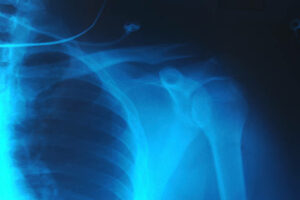

Dislocated Shoulder: What to Do and How to Treat it?

A dislocated shoulder is what its name depicts. It is a fairly common and sudden onset type of injury in which the upper arm bone pops out of the shoulder socket, either partially or fully. A shoulder can dislocate in any direction – forward, backward, or downward. However, forward dislocation of [Read More]